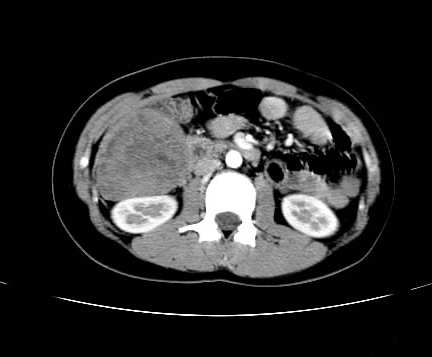

女 16岁  右上腹痛一天,无其他不适

右下腹巨大肿快,密度不均匀,内见坏死低密度区,边界清楚,与周边胀器明显有分界,未见强化,多考虑来源于间叶组织的良性肿物.

病灶巨大,少部分向肠腔内生长,大部分向长腔外生长。其密度不均匀,增强显示明显不均匀强化,并见有大片状始终不强化的不规则坏死液化区。虽然病灶中上部形态尚可,病人又如此年轻,但中下部形态、密度、强化特点强烈提示为恶性病灶。综上,我考虑本病例为:恶性胃肠道间质瘤。